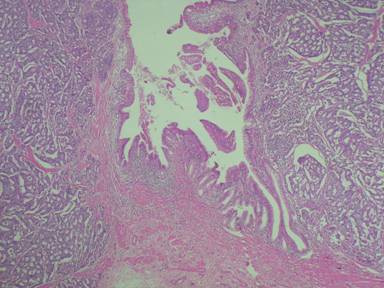

A 63-year-old male had two episodes of acute pancreatitis by biochemistry and abdominal ultrasonography. EUS findings showed an ampullary mass and cystic dilatation of terminal portion of duct of Wirsung suggestive of wirsungocele (Figures 1 and 2). EUS guided FNA from the ampulla suggested a neuroendocrine tumor. MRCP confirmed EUS findings of wirsungocele and ampullary mass (Figure 3). ERCP (Figure 4) and endoscopic ampullectomy was then performed and patient made an uneventful recovery. The histopathological examination and immunohistochemistry showed neuroendocrine tumor (pathological classification: G1) with cells expressing synaptophysin and chromogranin (Figure 5). The Mib proliferation index was less than 2%. The pancreatic duct was seen well dilated within the tumor tissue.

Figure 5. Microphotograph showing neuroendocrine tumor at the ampulla. The pancreatic duct is also seen. (Magnification, x40). |